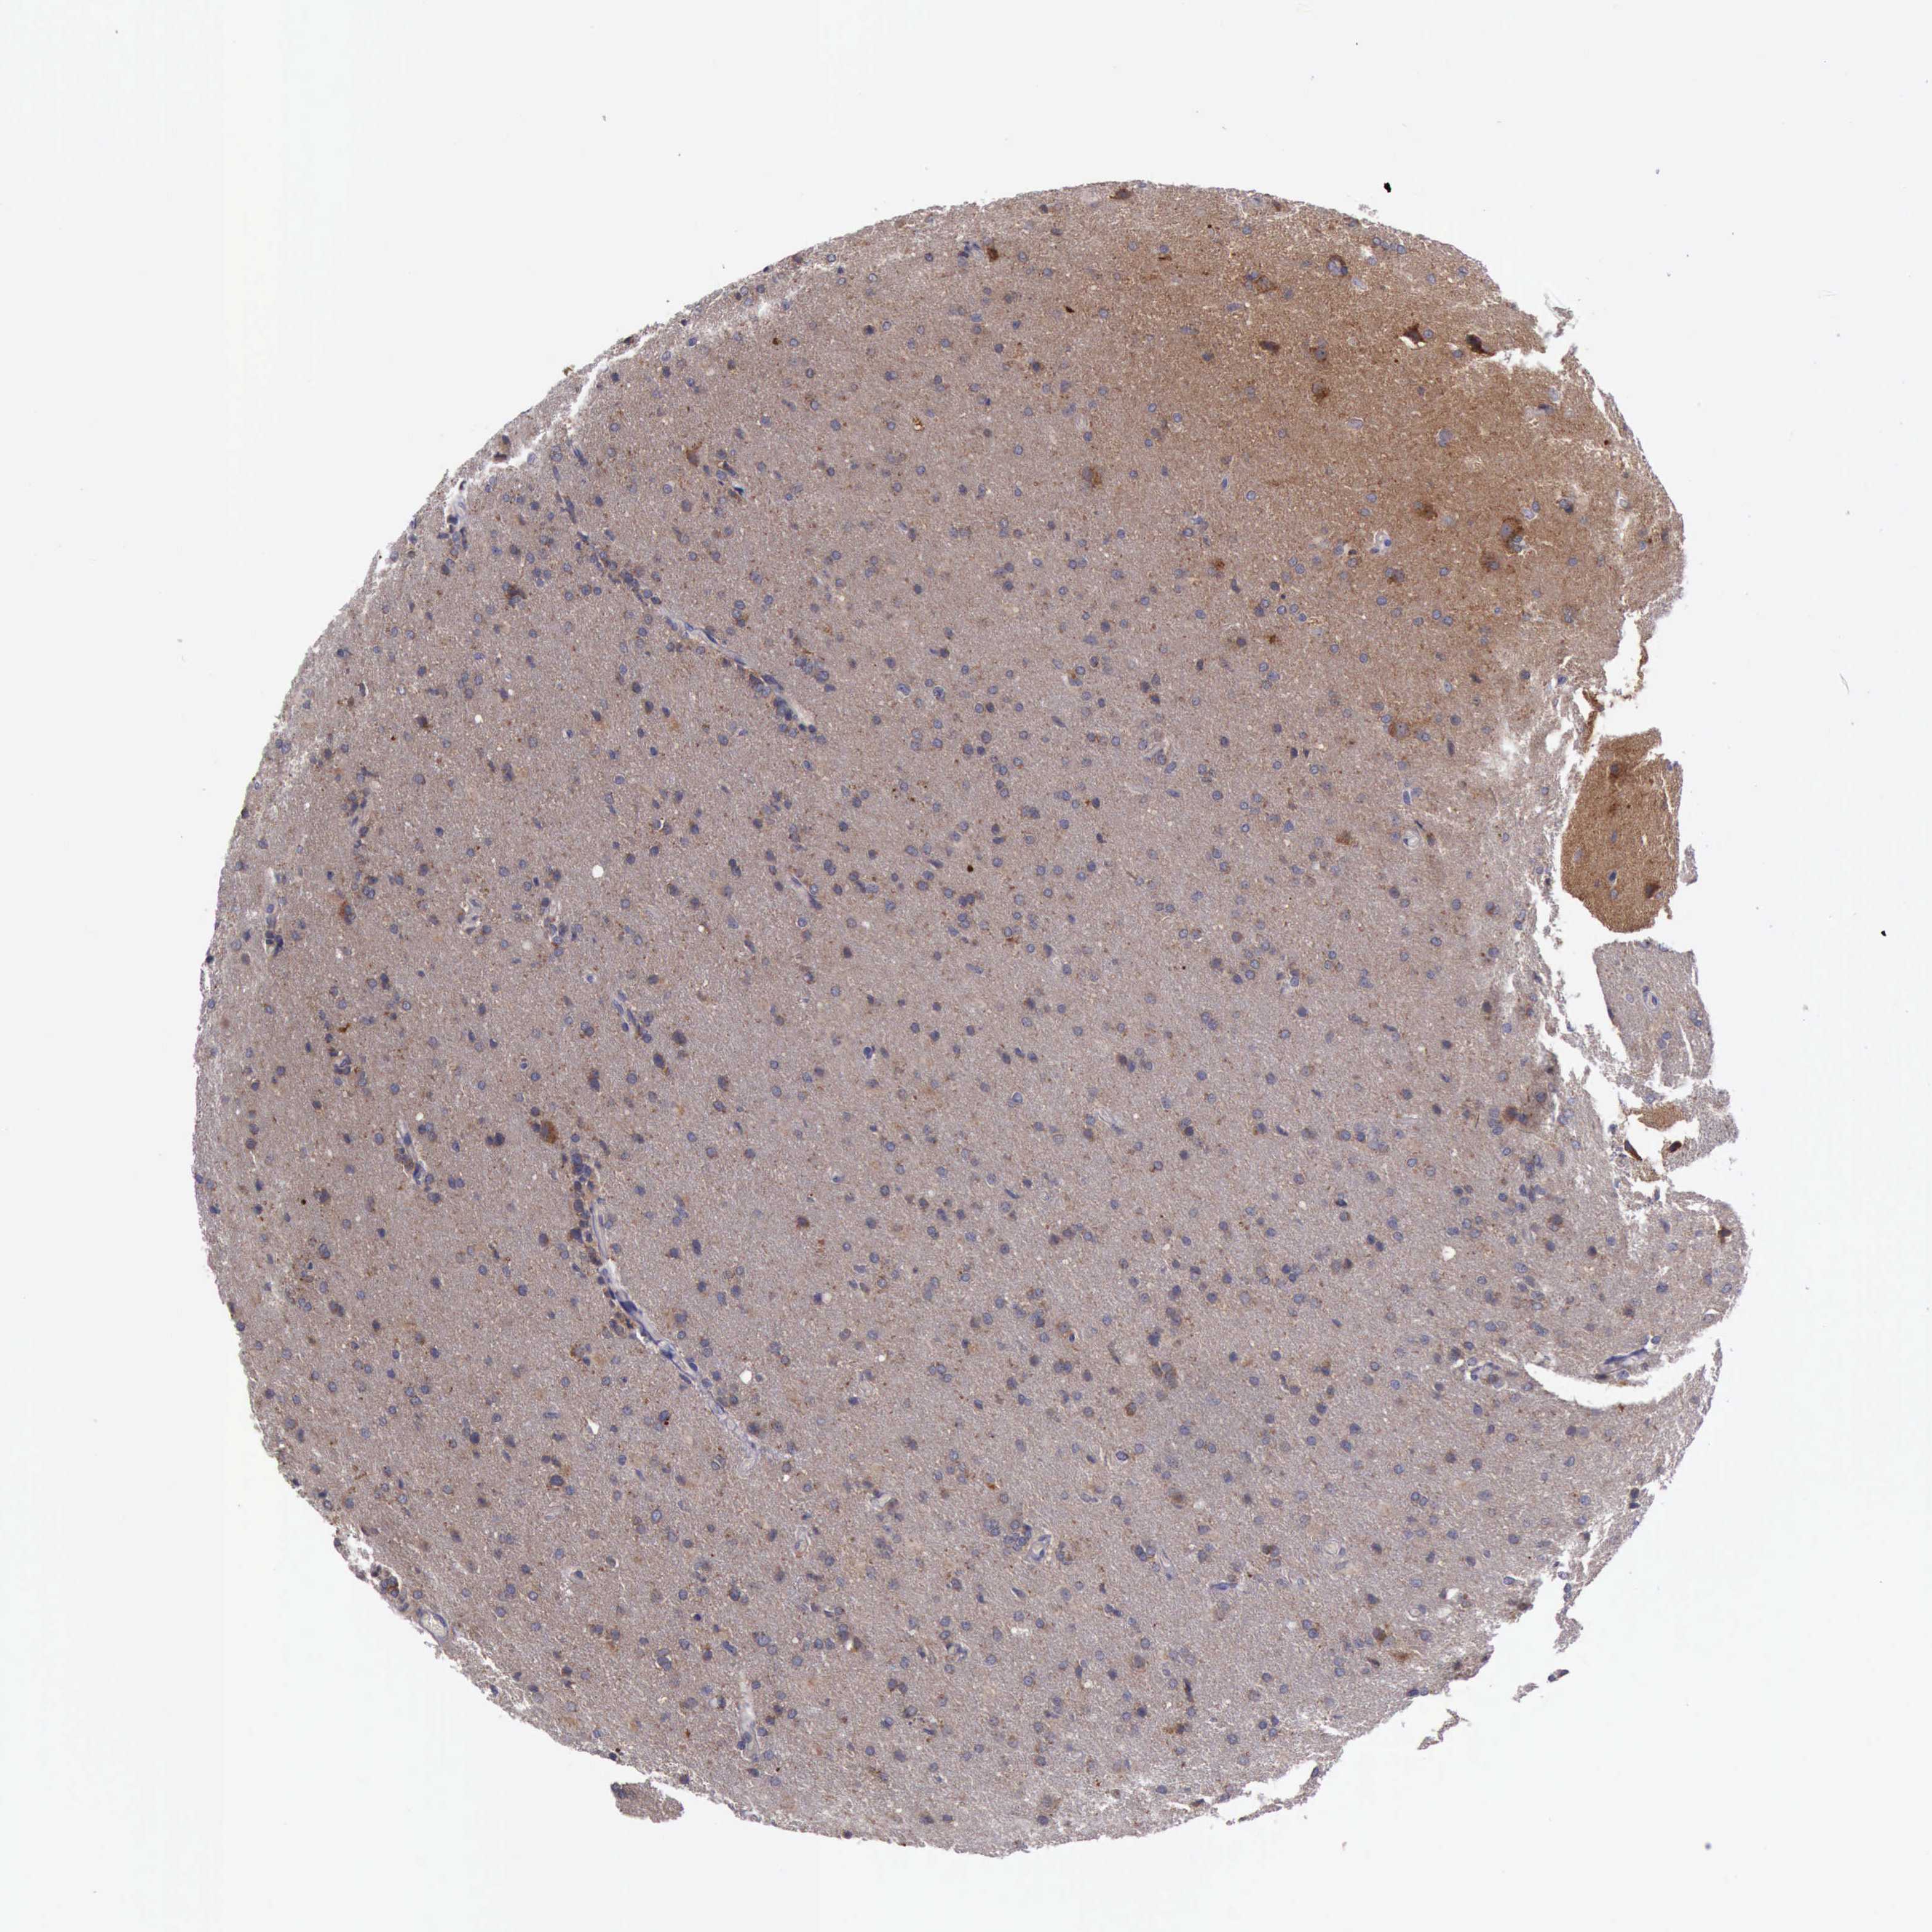

GLIOMA - Protein expressioni

A mouse-over function shows sample information and annotation data. Click on an image to view it in a full screen mode. Samples can be filtered based on level of antibody staining by selecting one or several of the following categories: high, medium, low and not detected. The assay and annotation is described here.

Note that samples used for immunohistochemistry by the Human Protein Atlas do not correspond to samples in the TCGA dataset.

Antibody stainingi

Antibody staining in the annotated cell types in the current human tissue is reported as not detected, low, medium, or high, based on conventional immunohistochemistry profiling in selected tissues. This score is based on the combination of the staining intensity and fraction of stained cells.

Each image is clickable and will lead to virtual microscopy that enables deeper exploration of all samples and also displays staining intensity scores, fraction scores and subcellular localization as well as patient and tissue information for each sample.

Antibody HPA001114

Antibody HPA042505

Staining

High

Medium

Low

Not detected

Intensity

Strong

Moderate

Weak

Negative

Quantity

>75%

75%-25%

<25%

None

Location

Nuclear

Cytoplasmic/membranous

Cytoplasmic/membranous,nuclear

Glioma, malignant, High grade

Glioma, malignant, Low grade